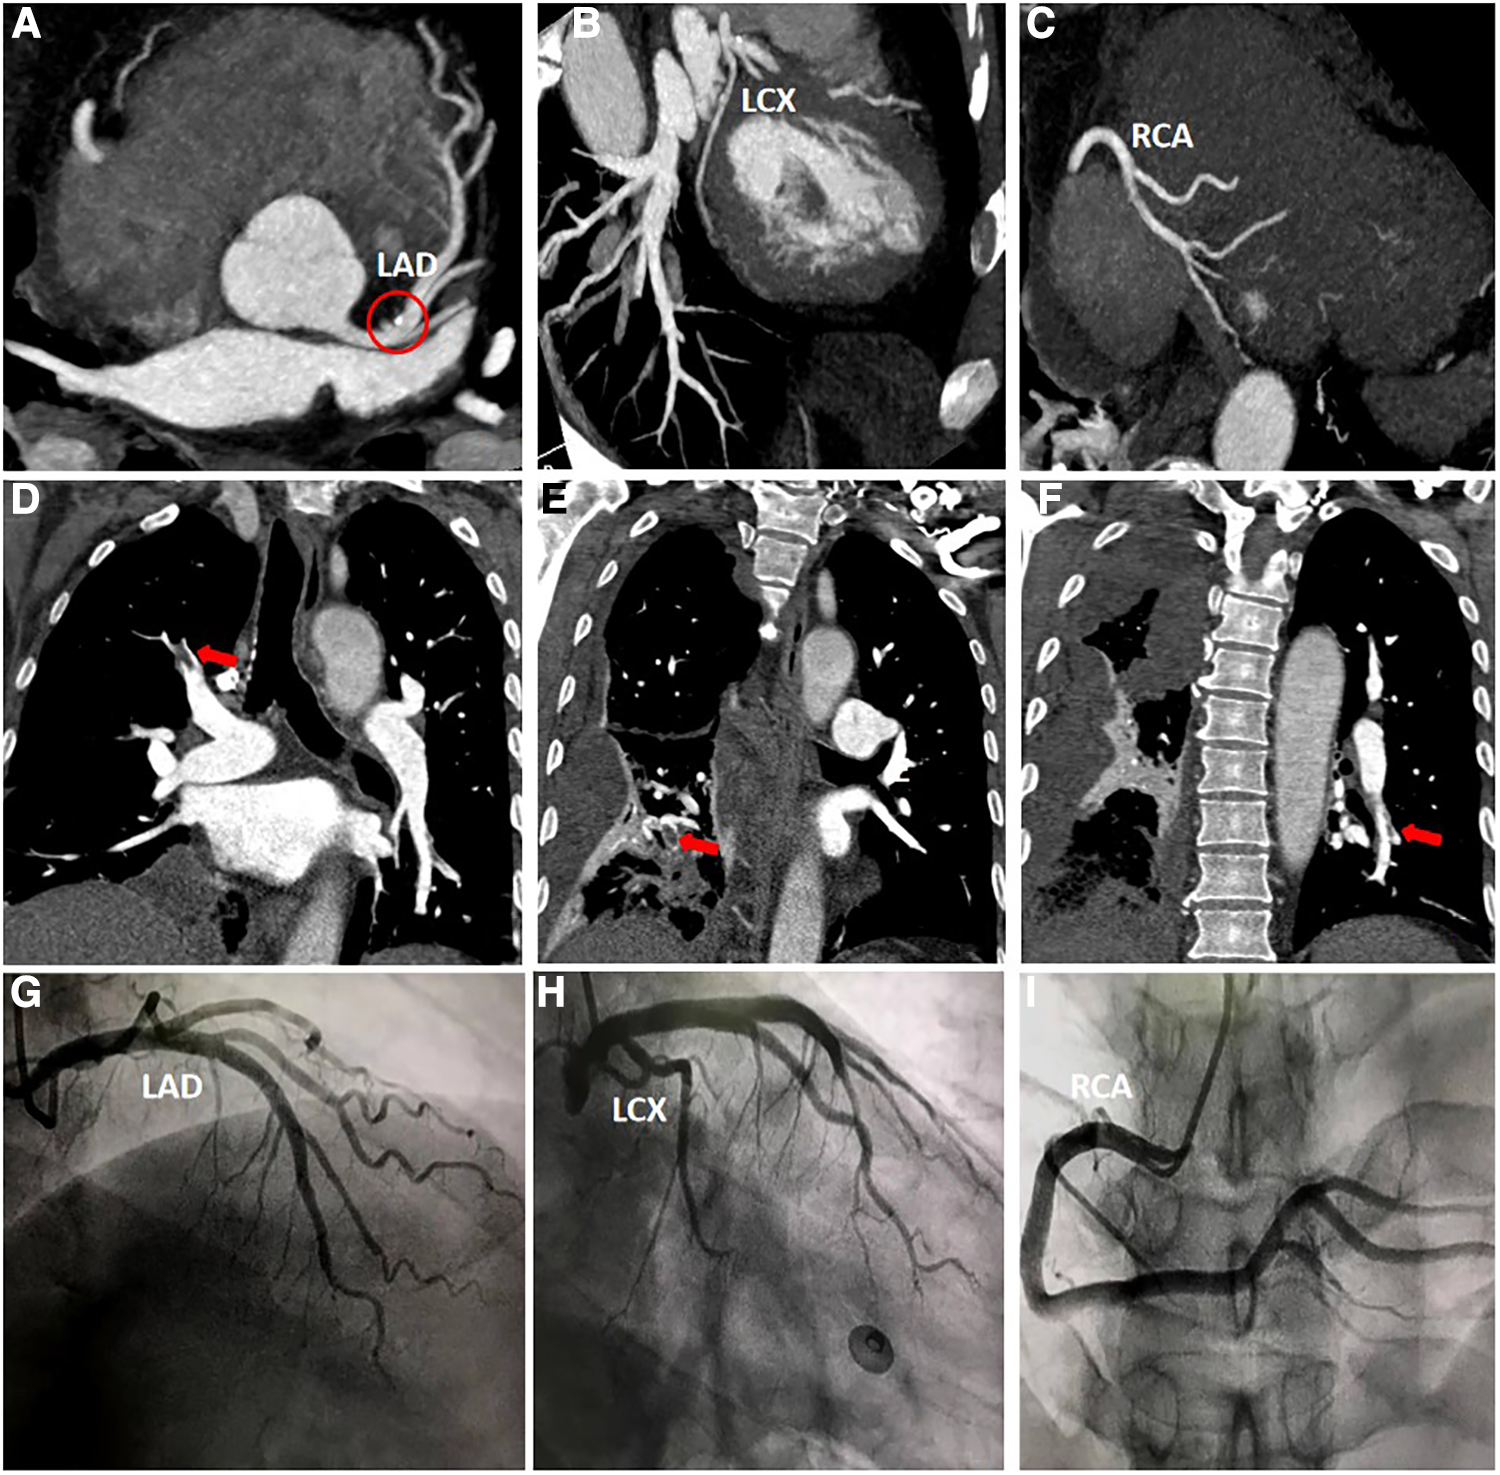

Furthermore, the patient was transferred to the Cardiology Department, where an emergency bedside echocardiography was performed. The echocardiogram showed that the diameters of the aorta and pulmonary arteries were within the normal range. Additionally, in the resting state, there were no definite segmental motion abnormalities observed in the left ventricular (LV) wall. Furthermore, there was no presence of pericardial effusion. The systolic function of the LV was found to be normal. At this point, ST segments of the inferior wall leads displayed resolution (Figure 1C), and the patient stated that the chest pain had subsided. Due to the presence of ICH, the Department of Neurosurgery suggested that anticoagulants should not be given for two weeks As a result, instead of performing a coronary angiography (CAG), we decided to proceed with a computed tomography coronary angiography (CTCA) to assess if there was any stenosis in the coronary artery. Surprisingly, the CTCA scan showed no signs of coronary artery occlusion or severe stenosis (Figures 3A–C). In addition, there were no identifiable factors present in the patient that could have caused coronary artery spasm. Furthermore, conditions such as AMI resulting from inadequate blood supply to the heart due to hypotension or anemia were ruled out.

Figure 3

(A–C) Computed tomography coronary angiography scan. Calcification can be seen in the left anterior descending artery (red circle), and no other abnormalities were observed. (D–F) Computed tomography pulmonary angiography scan. The main findings revealed the presence of thrombi in the right upper lobe, right lower lobe, and left lower lobe. (H–J) Coronary angiography scan. The scan indicates that there are no significant narrowings or stenosis observed in either the left or right coronary arteries.

However, a coagulation function test revealed a D-dimer level of 22.48 mg/L in the patient's blood. During the patient's hospitalization, the presence of hemoptysis and deep vein thrombosis (DVT) in their lower extremity were observed. Based on these symptoms, a possible diagnosis of PE was considered. To confirm this diagnosis, a computed tomography pulmonary angiography (CTPA) was performed (Figures 3D–F), and the diagnosis of PE was confirmed.

After successfully managing the ICH, the patient's condition stabilized, and he was discharged. He was prescribed oral warfarin for approximately 6 months, which gradually relieved his tightness in breathing symptoms. During his second hospitalization, a series of tests were conducted including biomarkers for myocardial injury, coagulation function assessment, echocardiography, CTPA and CAG. Importantly, the CTPA scan showed no abnormalities, indicating the absence of PE. Furthermore, the CAG results revealed no significant stenosis in the coronary arteries (Figures 3H–3J).